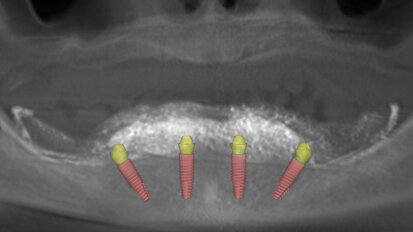

Motivated by his desire to simplify the treatment process for patients, Dr Philip Tan has developed a full-arch implant-retained prosthesis for completely ...

Treatment of edentulism with Pro Arch BLX focus of free webinar

LONDON, UK: When it comes to implants, the Straumann Group has been one of the major dental brands leading the way. In a free upcoming Straumann Group ...